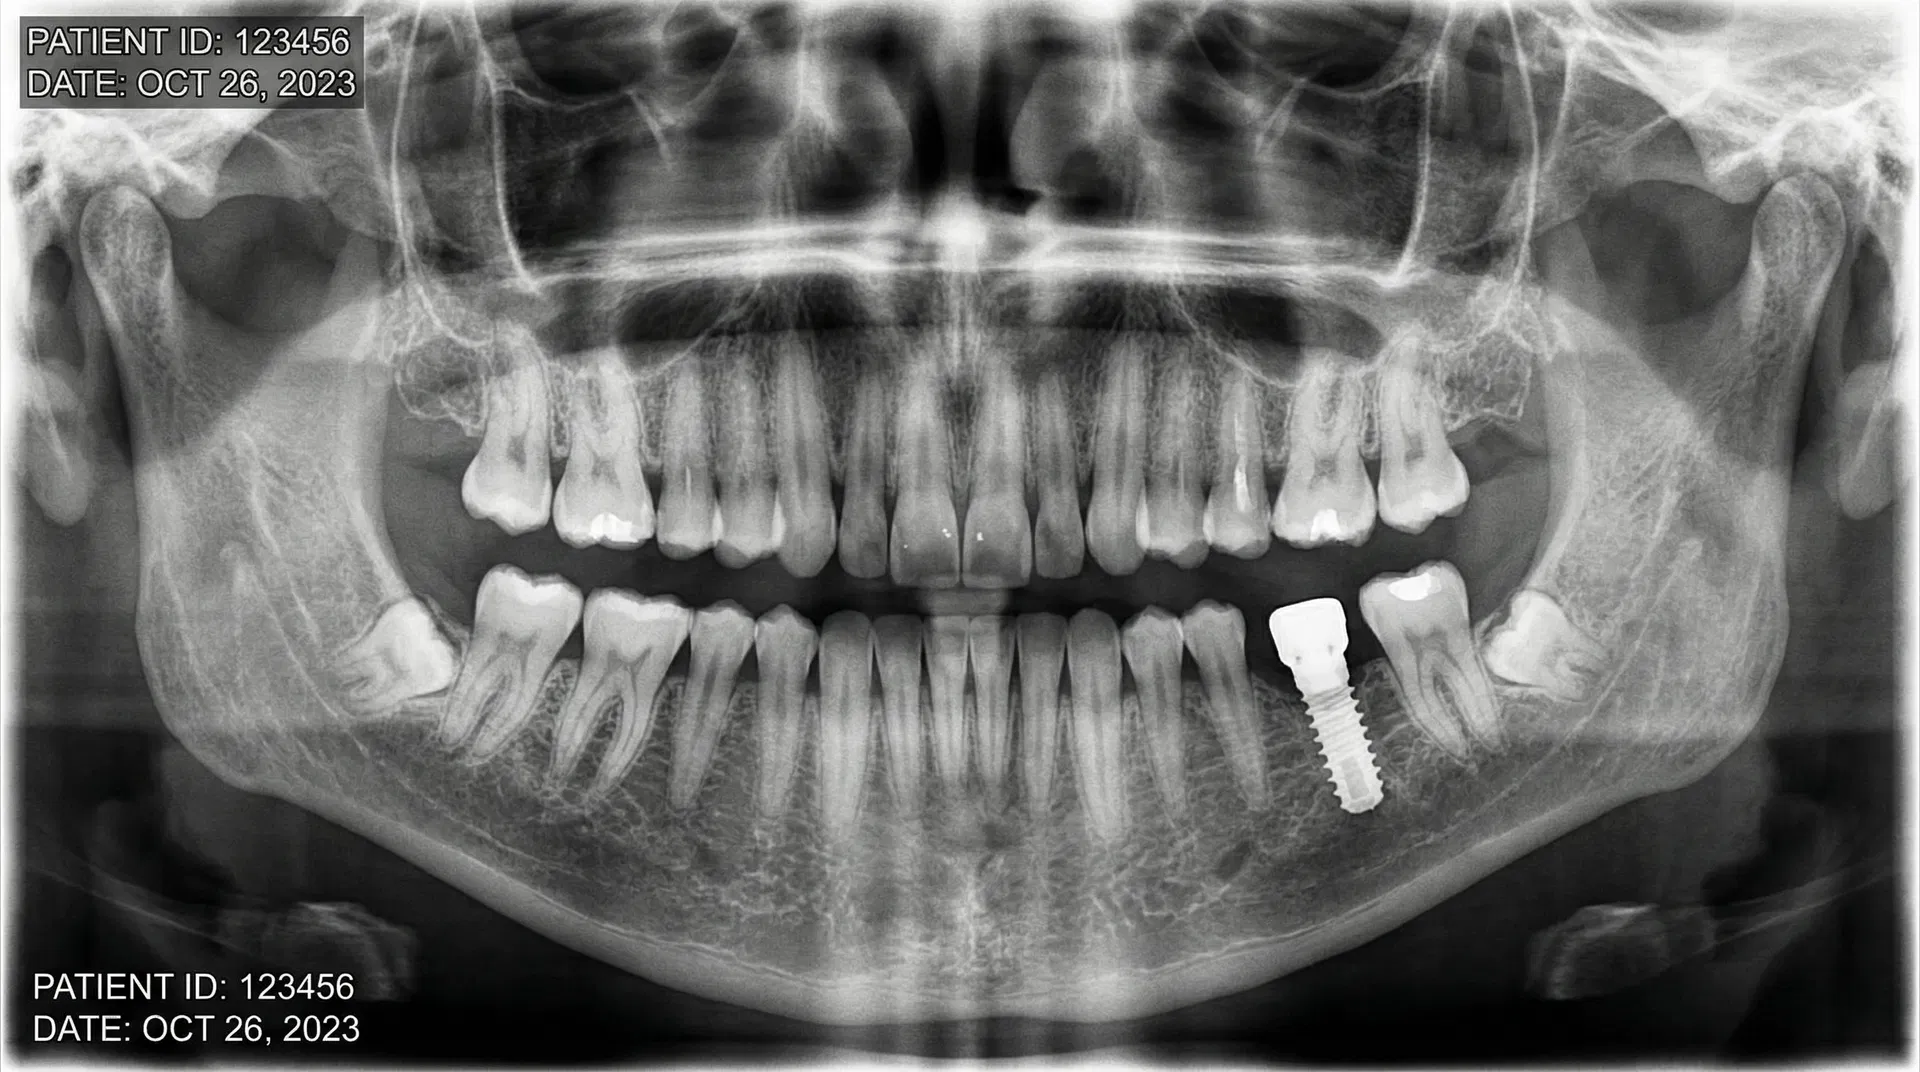

Before & After Transformations

See the life-changing results achieved by Dr. Nurein. Drag the slider to compare before and after treatment photos.

Note: Cases 2, 3, and 4 feature real patient results. Other cases are illustrative. Actual results may vary. Consult Dr. Nurein for a personalized assessment.

Single Tooth Implant

Missing upper front tooth replaced with a premium titanium implant and porcelain crown, restoring a natural, seamless smile.